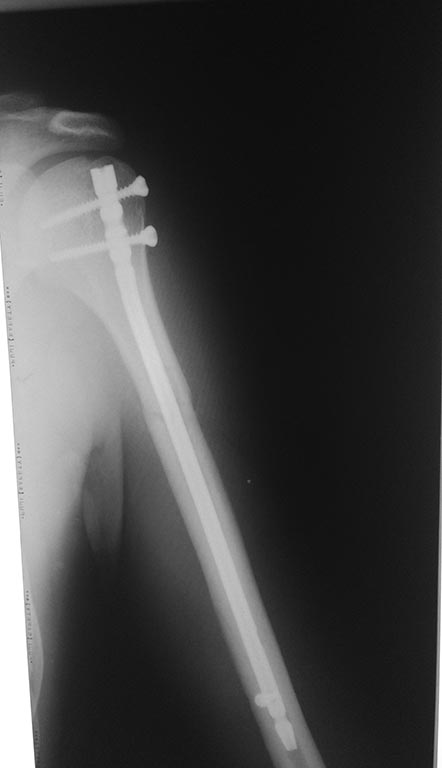

Доброго времени суток! Я умудрился на соревнования по троеборью на жиме лёжа в первом же подходе сломать плечевую кость,

причём на весе, который не на одно повторение делал в зале.... Благо мышцы и связки все целые остались, поломал как раз в том месте где грудь крепится. Меня прооперировали вставили титановый штифт во внутрь кости, снизу и сверху закрепили болтами, врач сказал что можно штифт оставить. Вопрос: смогу ли я вообще выйти на те же веса в жиме и тяге, которые были до травмы и рости дальше в силовых? И третье стоит ли вообще снимать штифт, по крайней мере вытаскивать нижний болт, т.к. из-за него будет создаваться повышенная нагрузка на кость и не треснет ли она в том же месте? Правильно ли срастается кость? Ничего страшного что она сместилась немного и не приведёт ли это к перелому снова? снимок сделан спустя 3 недели после операции

Сделано все неплохо.